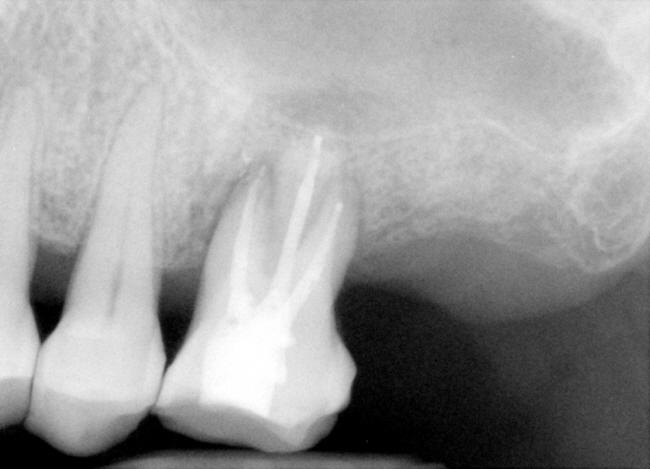

| 图一 术前根尖片左上6号牙根尖阴影阳性 | 图二 术前根尖片左上6号牙根尖阴影阳性 |

治疗:局麻,超声洁治4,5,6号牙,橡皮障隔离,开髓,活髓,使用特殊Piezo超声金刚钻头寻找MB2根管口,但是没有找到。使用根尖定位仪,用手用扩大针至15号,然后是用电动扩大针(Dentsply Tulsa Protaper),MB(近中根管),DB (远中根管)扩大到30/.06(锥度)14.5mm, P (鄂侧根管)40/.06 14.5mm,使用大量漂白液(sodium hypochlorite)冲洗和润滑剂,插入相应的主牙胶尖,拍摄根尖片(图三),距离尚可,P 根管最后通到 15mm,用纸尖吸干根管,介入AH Plus paste糊剂,再次插入相应的主牙胶尖,加入附加牙胶尖,侧方挤压充填,再次拍摄根尖片(图四),P根尖可能糊剂超充,去除多余牙胶尖,做轻度垂直挤压充填,使用Cavit暂时封闭根管治疗开口。治疗过程,林太太恶心两次,血压正常,自行好转。

2010-1-22 病人回诊所仍觉得疼痛没有改善,冷热痛,夜间痛,要求拔牙,检查表明:左上6号牙有轻度扣痛,颊侧根分叉处,以及鄂侧根鄂面有探痛,分析术前X光片(图八),好像远中根牙胶尖充填不到位,可能是术后疼痛原因,残余牙髓炎,所以我们准备作根尖切除术。翻瓣,根尖骨板完整,用高速牙钻开窗,一时找不到远中根尖,再拍一张根尖片(图九),适当调整后,我们找到了远中根尖,并作了切除术(图十),然后根尖倒充(IRM,图十一),生理盐水冲洗,缝合伤口。